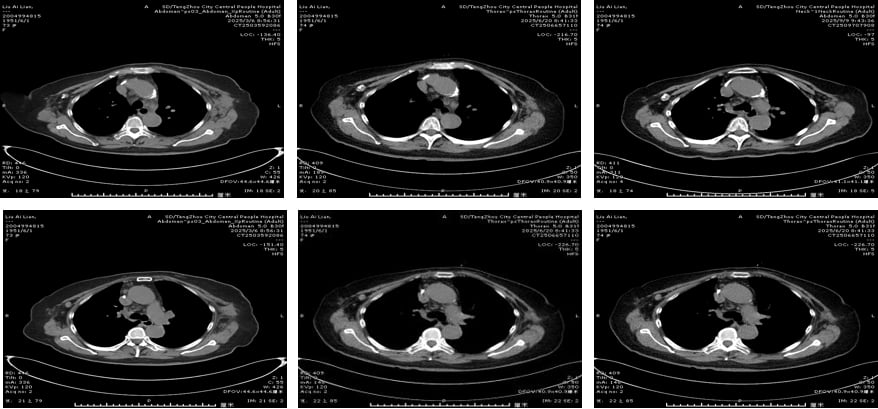

二线治疗(2018.8-2023.3):局部复发,靶向联合放疗精准打击

2018年8月,患者右乳下方出现多发皮肤结节,提示局部复发。此时,医生选择了全身靶向治疗与局部放疗相结合的策略。全身治疗方案为小分子酪氨酸激酶抑制剂(TKI)吡咯替尼联合内分泌药物氟维司群。吡咯替尼能够多靶点抑制HER2、EGFR等受体,进一步阻断癌细胞生长信号。局部放疗则针对复发病灶进行精准清除。经过治疗,皮肤结节明显缩小,红肿消退,疾病控制稳定,且无严重不良反应。这一阶段的治疗长达近5年,充分说明了多线治疗的有效性和患者的良好耐受性。

三线治疗(2023.3-2024.7):对侧乳腺新发病灶,双靶联合化疗再出击

2023年3月,患者左乳发现新发肿物及腋窝淋巴结肿大,经穿刺活检证实为左乳浸润性导管癌,同样是HER2阳性。考虑到患者年龄及基础疾病,她拒绝了手术。医生再次调整方案,采用了帕妥珠单抗、伊尼妥单抗双靶联合卡培他滨化疗。帕妥珠单抗是另一种HER2靶向药物,与曲妥珠单抗作用机制互补,形成双重阻断,能更有效地抑制HER2信号通路。伊尼妥单抗也是一种新型的HER2靶向药物。这一方案持续了10个周期,左乳肿物明显缩小,腋窝淋巴结也得到控制,评估为部分缓解(PR)。

四线治疗(2024.7-2025.2):ADC药物登场,恩美曲妥珠单抗显身手

2024年7月,患者因冠心病、房性早搏就诊心内科,治疗一度中断。待心脏问题稳定后,医生引入了抗体偶联药物(ADC)——恩美曲妥珠单抗(T-DM1)。ADC药物是一种“导弹式”的精准打击武器,它将靶向抗体(如抗HER2抗体)与高效化疗药物(如DM1)偶联,通过抗体识别癌细胞表面的靶点,将化疗药物精准递送至癌细胞内部,减少对正常细胞的损伤,从而提高疗效并降低全身性副作用。经过4个周期的T-DM1治疗,患者病情稳定(SD),仅出现轻度乏力、血小板减少,耐受性良好。

五线治疗(2025.3-至今):德曲妥珠单抗持续抗癌,疗效显著

2025年3月,患者开始接受目前最先进的ADC药物之一——德曲妥珠单抗(T-DXd)治疗。德曲妥珠单抗同样是ADC药物,它将抗HER2抗体与拓扑异构酶I抑制剂偶联,具有更高的药物抗体比(DAR),意味着每个抗体携带的化疗药物更多,且其化疗载荷在肿瘤微环境中释放后,还能穿透细胞膜,对周围的癌细胞产生“旁观者效应”,进一步增强抗肿瘤活性。截至目前,患者已接受9个周期的T-DXd治疗,左侧腋窝淋巴结较前变小,左乳不规则软组织密度范围缩小,病情持续稳定,且不良反应轻微,耐受性良好。这再次证明了新一代ADC药物在HER2阳性乳腺癌后线治疗中的卓越疗效和安全性。